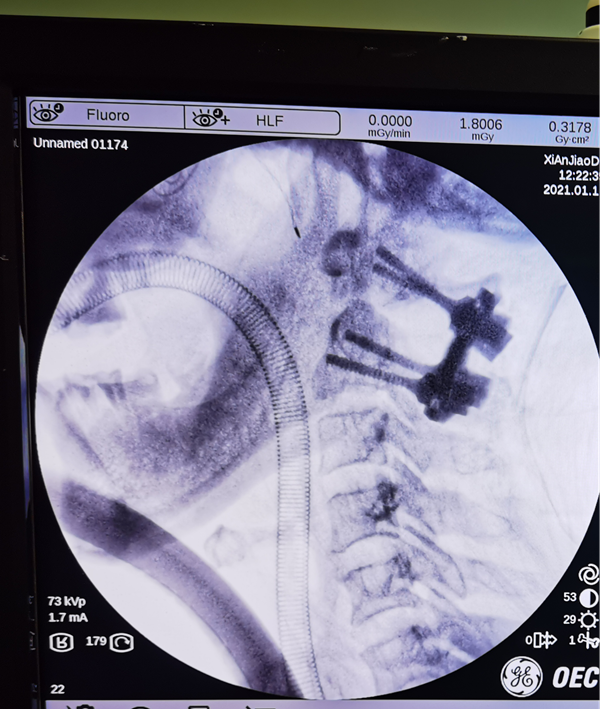

经过骨三科详细分析讨论后后,张纯主任医师、王伟卓副主任医师为患者精心设计了手术方案,术前3D打印制定了模板。1月10日,在麻醉科、手术室等医务人员的密切配合下,韩新生教授麻醉,张纯主任医师主刀、王伟卓副主任医师、曾思想、黄思华主治医师为患者实施手术。术中王芳为患者实时肌电监护。经过 3小时的精心操作和努力,成功为患者行了颈椎后路寰枢椎椎弓根螺钉内固定及寰枢植骨融合术,术中患者出血不到200ml,手术取得圆满成功。